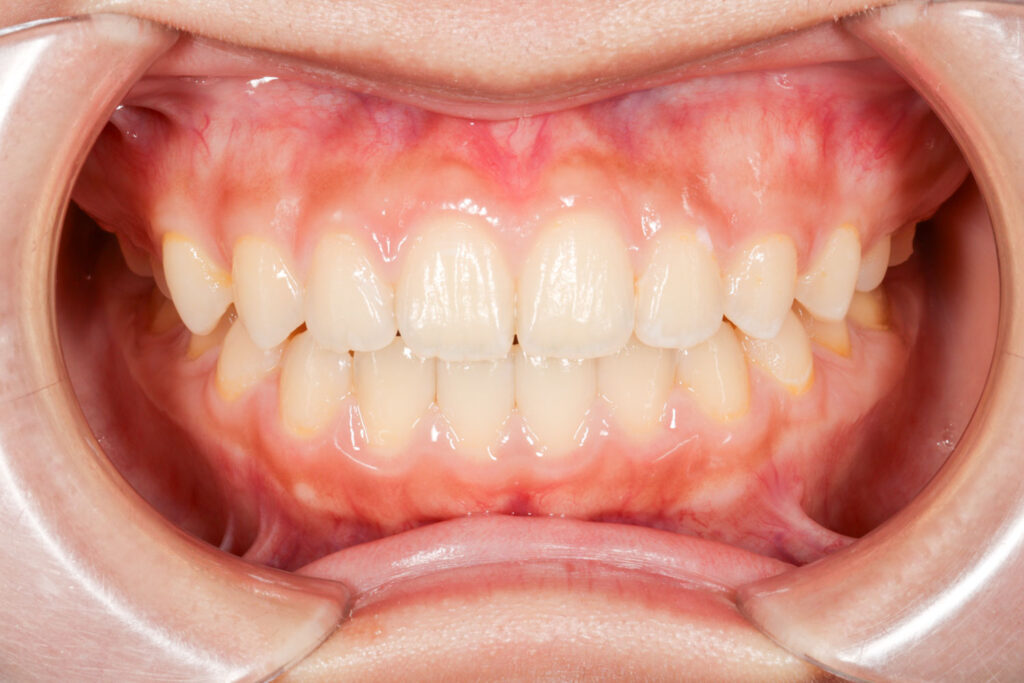

Before

After

年齢 10代

治療装置 上は裏側の矯正装置(フルリンガル)

治療内容 非抜歯

治療期間 2年8か月

リスク 歯の移動に伴う痛み、歯肉退縮、歯根吸収、歯肉炎、虫歯

主訴 ガタガタと隙間が気になる

症状 叢生と正中離開

治療回数 36回程度

総額費用 140万円程度